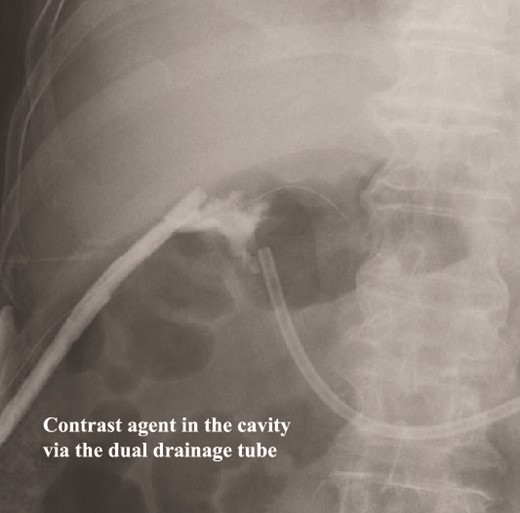

The amylase levels of drainage fluid and blood at postoperative day (POD) 1 (Ascites 6980 IU/dl, Serum 1123 IU/dl) and POD 3 (Ascites 673 IU/dl, Serum 487 IU/dl) revealed pancreatic fistula based on the criteria of International Study Group of Pancreatic Fistula [2]. After that, their results improved, and fluoroscopy showed no stenosis and leakage. Therefore, we removed all drains at POD 8, however the following day, the patient developed high fever. Plain CT revealed intraperitoneal fluid around subdiaphragmatic and duodenal stump (Fig. 3). We inserted a pig-tail drainage tube to the subdiaphragmatic space (Fig. 4). Since biliary fluid was discharged through the tube, we suspected duodenal leakage and started infusion of somatostatin analogs and antibiotics. At POD 13, the patient complained of whole abdominal pain with peritoneal signs. As the patient became hemodynamically unstable, we performed emergent laparotomy to lavage and insert multiple drainage tubes. Two perforation pinholes were identified in the anterior wall of the duodenum, near the stump. We resected the vulnerable duodenal stump including the perforation site and closed by Gambee’s method with unabsorbable 4–0 proline (Fig. 5). We inserted multiple drainage tubes (Fig. 6a): a C-tube from the cystic duct into the common bile duct to separate biliary juice and pancreatic juice, a dual drainage tube around the duodenal stump with continuous suction (Fig. 6b), a simple intraluminal drainage tube via the duodenum near the stump through a new skin incision on the left side of the abdomen for duodenal decompression, and a drainage tube into the rectovesical pouch. After the reoperation, we irrigated the cavity around the duodenal stump through each drain with saline. Since the contrast agent did not flow into the duodenum and the cavity around the duodenal stump gradually got smaller (Fig. 7), oral intake of fluid diet was initiated at POD 37. However, fistulography at POD 44 showed that the fistula of duodenal stump had relapsed (Fig. 8). Although we considered performing second reoperation for duodenal stump closure, due to the cavity around the duodenal stump was located, we continued conservative management and irrigation via drainage tubes. Fistulography demonstrated no leakage from the duodenal stump at POD 56, and the patient discharged at POD 59.

Fistulography reveals recurrence of the duodenal fistula. Fistulography at POD 44 showed recurrence of the duodenal fistula (arrows).